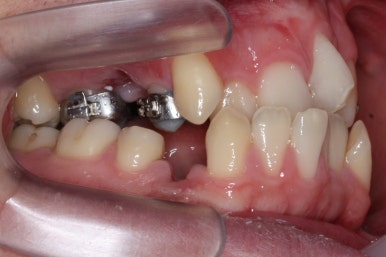

좁아져 있는 위턱뼈를 가로로 넓혀주기 위해서 악궁확장장치를 사용했습니다.

윗니는 선천결손으로 치아가 2개가 모자랐고 앞니도 거꾸로 물리는 상황이여서 아랫니도 균형있게 2개를 추가로 더 뽑았습니다.

악궁확장과 동반하여 부산구순구개열 키다리아저씨치과에서는 브라켓을 부착하여 가지런하게 하는 작업을 시작하였습니다.

위아랫니가 각각 가지런해지고 있는 것을 볼 수 있습니다.

적절한 시기가 되면 악궁확장장치를 제거하고, 확장장치가 걸려있던 치아도 가지런하게 해줍니다.

윗니는 아직 가지런하게 하는 작업 중이며, 아랫니는 가지런하게 하는 작업은 거의 다 되었습니다.